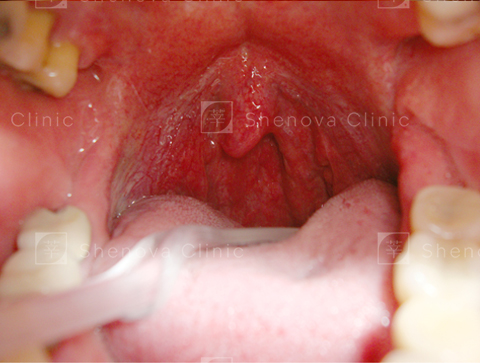

正常_軟硬顎、扁桃腺、懸壅垂位置圖01

正常

可見扁桃腺、軟顎、完整懸壅垂。